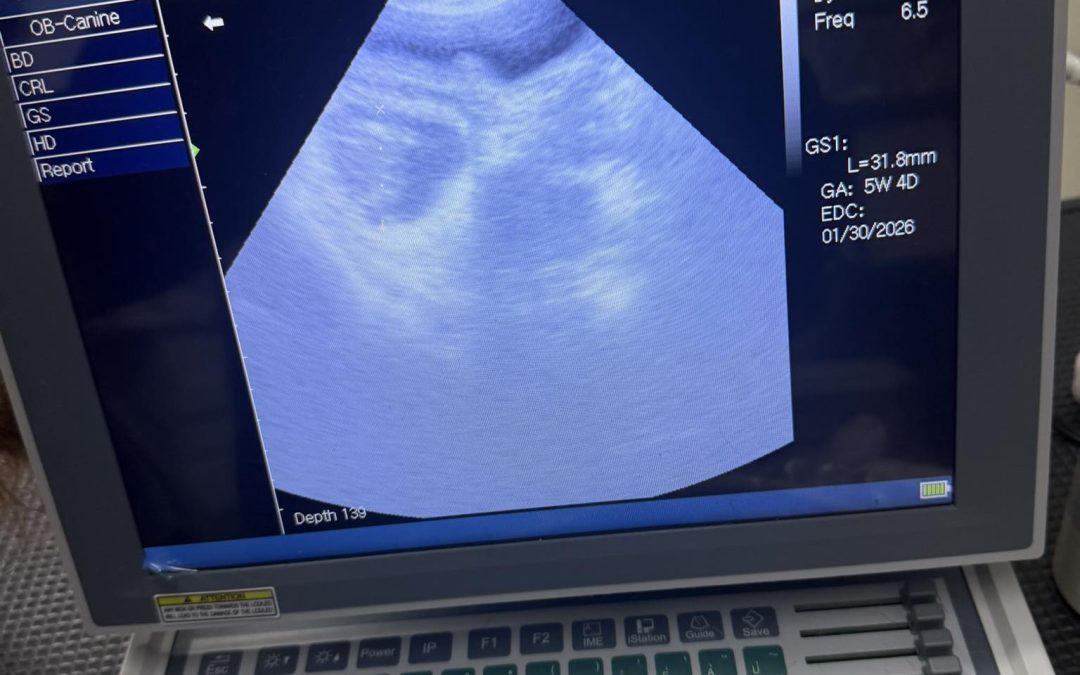

Service: Mobile Pet Ultrasound Blackburn Location: Blackburn,  Lancashire How We Helped: Preston’s K9 fertility services had the pleasure of meeting these gorgeous babies today I carried out a ultra sound scan on their mummy and confirmed she is pregnant Great...